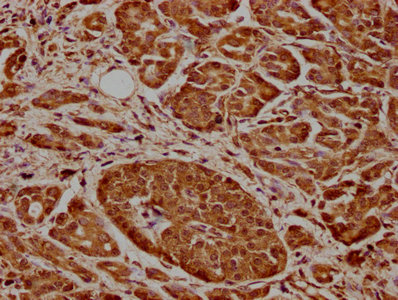

IHC image of CSB-PA28369A0Rb diluted at 1:600 and staining in paraffin-embedded human pancreatic cancer performed on a Leica BondTM system. After dewaxing and hydration, antigen retrieval was mediated by high pressure in a citrate buffer (pH 6.0). Section was blocked with 10% normal goat serum 30min at RT. Then primary antibody (1% BSA) was incubated at 4°C overnight. The primary is detected by a biotinylated secondary antibody and visualized using an HRP conjugated SP system.